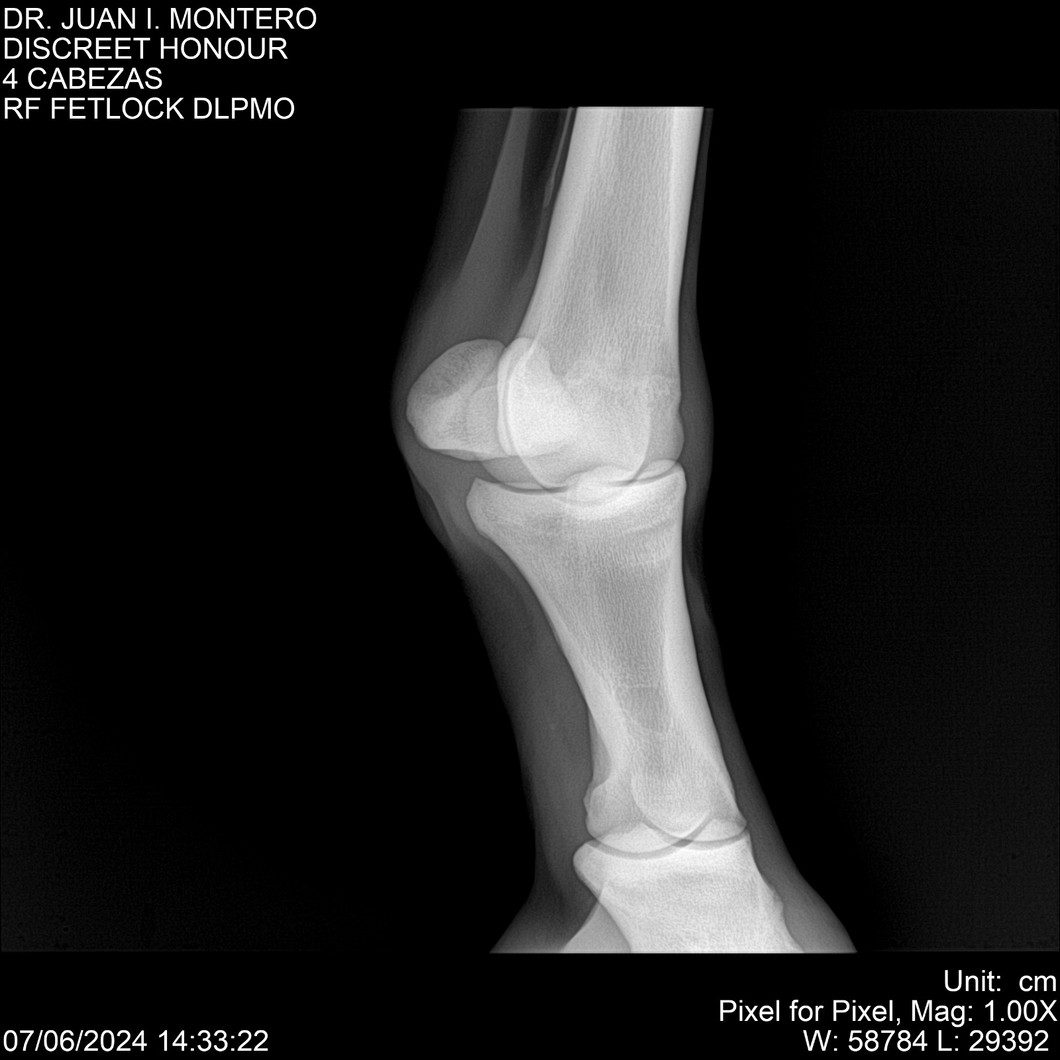

LOTE 6, DISCREET HONOUR 🔥 🔥 🔥 Lote Anterior Volver al remate Lote Siguiente Ficha Contacto Montevideo - Ficha del Lote Identificador: #281093 Categoría: Yeguarizos Montevideo - 82 Visualizaciones ClicData Contacto Empresa: Abelenda N. R., Walter Hugo Nombre*: Teléfono* : E-mail* : Mensaje Enviar Registrese gratis Este contenido Exclusivo está disponible sólo para usuarios registrados Ingresar